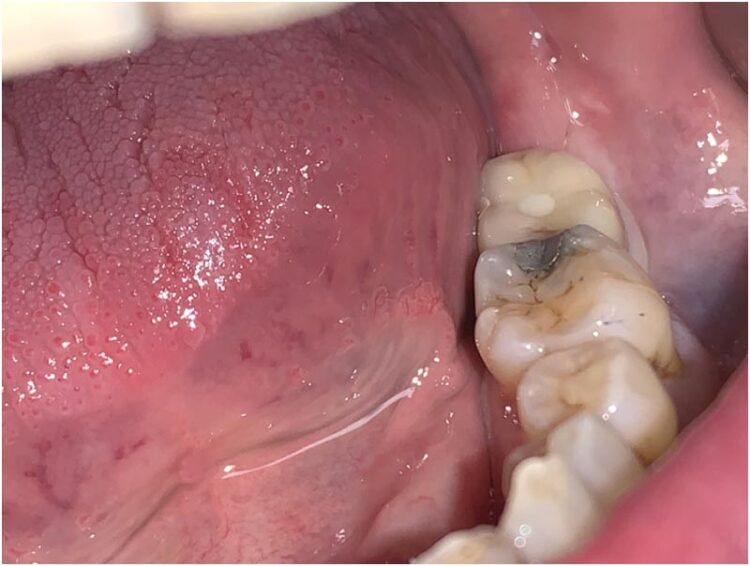

This 53-year-old, medically fit and well male patient attended complaining of pain and tenderness from his lower left second molar. Clinical and radiographic examination showed this molar tooth to be broken down and unrestorable. It was decided that this tooth required extracting and the patient was keen to replace this gap with a dental implant.

This case beautifully demonstrates the emergence profile that the tissue level implants facilitate along with the ease of cleansability for the patient, even when the prosthesis is placed posteriorly in difficult to reach areas.